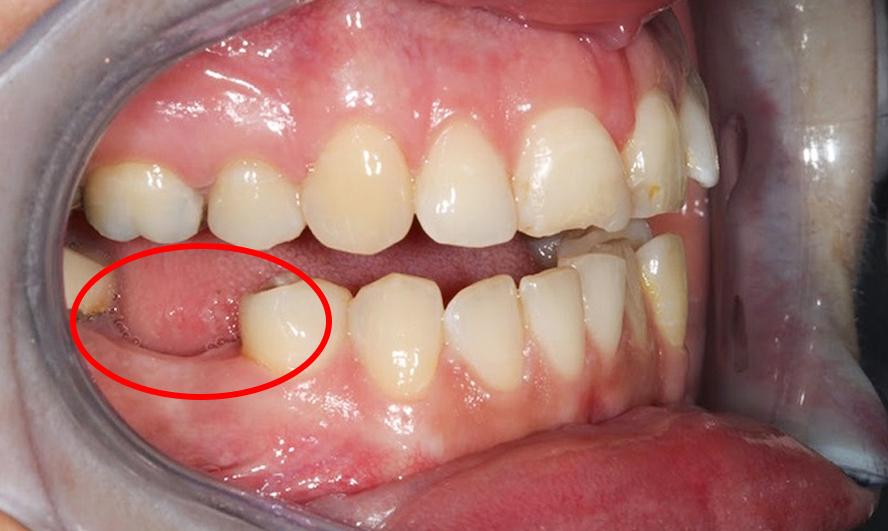

Các răng kế cận xô lệch, đổ nghiêng

Răng số 5 (phía trước) và số 7 (phía sau) có xu hướng nghiêng vào khoảng trống do răng số 6 để lại.

Sau một thời gian, kẽ răng hở, thức ăn nhét vào, dễ sâu răng và viêm nướu.

Ngoài ra, răng đối diện (ở hàm trên hoặc hàm dưới) trồi dài xuống khoảng trống vì không có điểm chạm nhai – gây lệch khớp cắn, đau cơ mặt.